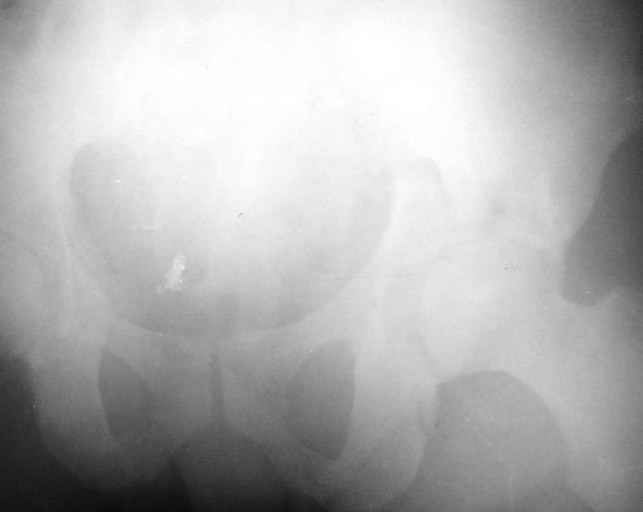

Сегодня на приеме был пациент, чьи начальный снимок напомнил обсуждаемый сейчас (см. выше). Снимки в других проекциях, показывающие истинный характер повреждения, ниже. Это inlet проекция (вход в таз) и запирательная проекция Judet.